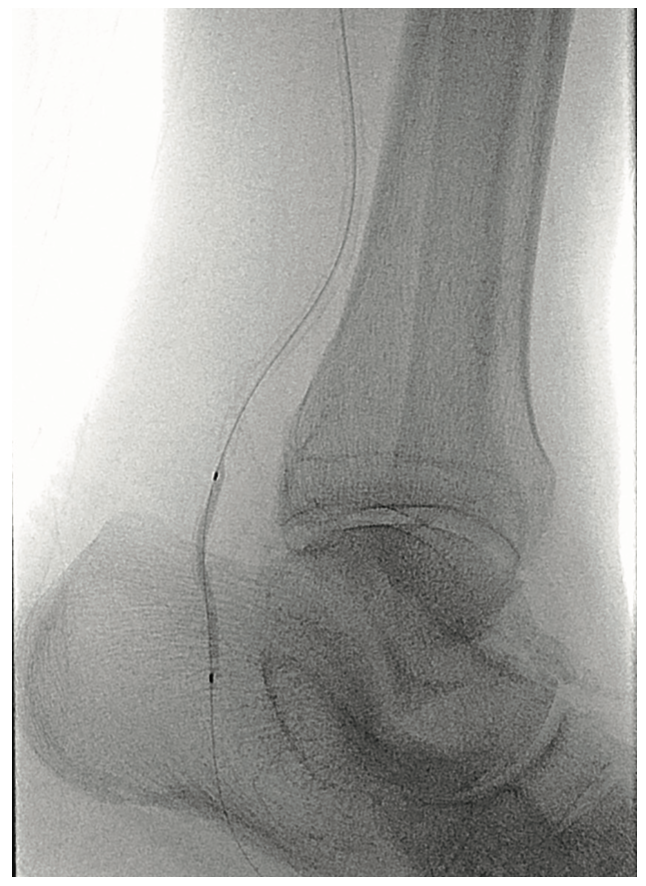

The patient was heparinized. A long 6 French Destination sheath (Terumo Interventional Systems) was used to cannulate the femoral-popliteal artery with an .035-inch system. We then selectively cannulated the posterior tibial artery with an .014-inch Grand Slam wire (Asahi Intecc). Using an .014-inch catheter and wire, we were able to pass through the distal posterior tibial artery stenosis into the pedal vessels. We started with a 2.0 mm plain balloon (POBA), resulting in recoil (Figures 3-4). We then used a 2.5 mm diameter Serranator PTA Serration Angioplasty Balloon (Cagent Vascular) (Figure 5) and achieved significant lumen gain without recoil. The peroneal artery lesion was also treated with angioplasty. The posterior tibial artery was considered to be the most important for wound healing, as the peroneal artery mostly terminated at the ankle level and the posterior tibial artery had strong dominant flow into the left foot. In addition, the anterior tibial and dorsalis pedis pathway was chronically occluded and essentially clinically nonexistent.